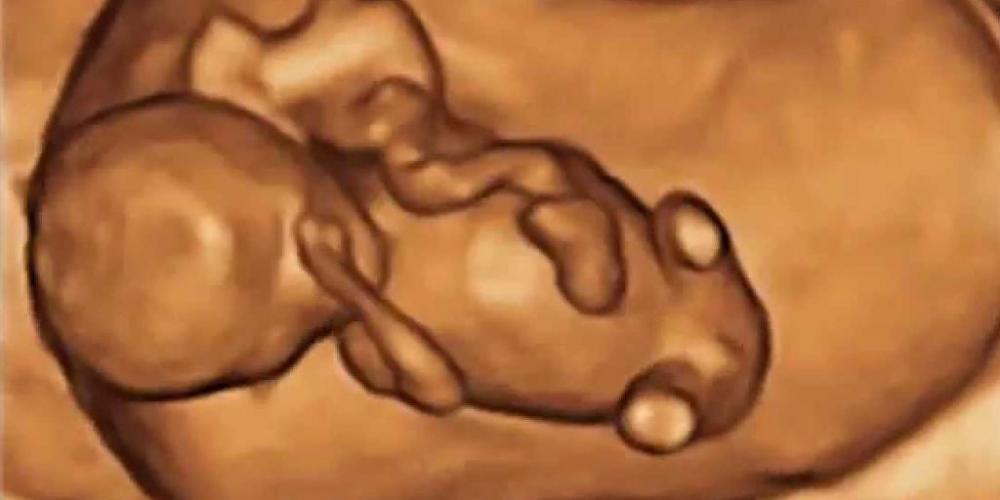

LA VIDA AVANZA EN EL VIENTRE DE LA MADRE

ASÍ COMIENZA LA MARAVILLA DE LA VIDA